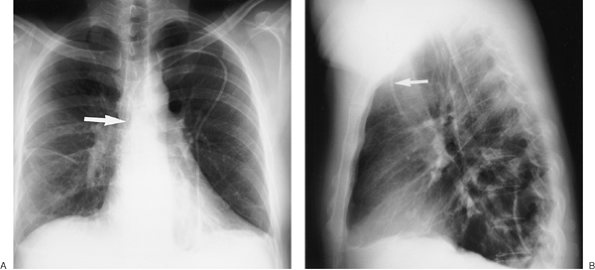

Numerous types of single- and dual-lead pacemakers and combination pacer–defibrillators are available. They are used to treat a variety of dysrhythmias. Accurate interpretation of their appearance on chest radiography requires knowledge of the specific type of pacemaker placed. The three major approaches to insertion of a pacemaker electrode into the heart include epicardial, subxiphoid, and transvenous implantations; transvenous is the most common. With single-lead pacers, the wire is placed into the right ventricle by way of the cephalic, subclavian, or jugular vein. When the lead is wedged into the myocardial trabeculae near the cardiac apex, the lead will be stable and have maximal contact with the endocardial surface. With dual-lead pacers, one lead is generally placed into the right atrium and the other into the right ventricle. It is important to know where the desired placement of leads is for each patient, because placement within the coronary sinus may be accidental or purposeful. After the electrodes are positioned, the generator is placed in a pouch in the subcutaneous tissues of the chest wall or beneath the pectoralis muscle. Biventricular pacemakers are used to treat congestive heart failure. Leads are placed in the right atrium and right ventricle, and a third lead is placed in the coronary sinus for pacing the left ventricle (Fig. 5-18).

FIGURE 5-18. Biventricular pacer. PA (A) and lateral (B) chest radiographs show normal positioning of lead tips in the right atrium (solid white arrow), right ventricle (dashed white arrow), and coronary sinus (solid black arrow).